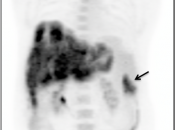

Recurrence & Restaging: (Most common indication)

- Rising tumor markers & negative (or indeterminate) CT scan.

- Restaging known recurrence, especially if surgery is contemplated.

- Distinguishing recurrence from post-therapeutic inflammation/scarring.

False Negatives:

- If there are multiple areas of intense bowel uptake (a common finding), the primary tumor can be difficult to locate — especially if the associated soft tissue lesion is small, which can be undetectable with CT imaging.

- Mucinous adenocarcinomas and necrotic tumors can have low avidity for FDG.